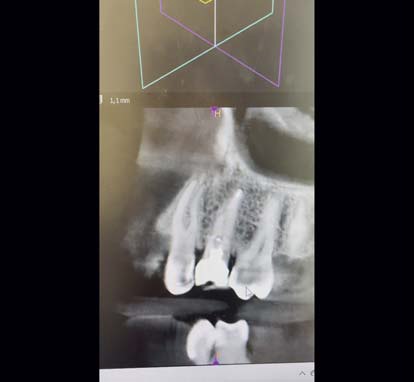

Każdy doświadczony endodonta marzy o przypadku leczenia trzykorzeniowego zęba przedtrzonowego w swoim endodontycznym portfolio. Co powoduje, że owa wariacja anatomiczna jest tak pożądana? Przede wszystkim to, że występuje bardzo rzadko. Po przeglądzie piśmiennictwa stwierdzono, że częstość występowania trzykorzeniowych zębów przedtrzonowych, nazywanych także little molars, wynosi 1-4% w przypadku pierwszych zębów przedtrzonowych oraz poniżej 1% w przypadku drugich zębów przedtrzonowych. W Polsce odsetek występowania trzykorzeniowych zębów przedtrzonowych w ogóle wynosi aż 9,2%. Leczenie trzykorzeniowych zębów przedtrzonowych należy do jednych z najbardziej wymagających i trudnych przypadków endodontycznych, nie tylko ze względu na bardzo rzadkie występowanie, ale i z uwagi na: trudności w diagnostyce, dostęp, instrumentację, odbudowę protetyczną, bardzo delikatną budowę korzeni. W pracy opisano trzy przypadki leczenia trzykorzeniowych zębów przedtrzonowych, w tym jeden opatrzono filmem.

Every experienced endodontist dreams of having a three-rooted premolar treatment case in his endodontic portfolio. What makes this anatomical variation so desirable? First of all, it is very rare. After reviewing the literature, it was found that the incidence of three-rooted premolars, also called little molars, is 1-4% in the case of fi rst premolars and less than 1% in the case of second premolars. In Poland, the percentage of three-rooted premolars is as high as 9.2%. Treatment of three-rooted premolars is one of the most demanding and difficult endodontic cases, not only due to their very rare occurrence, but also due to: difficulties in diagnosis, access, instrumentation, prosthetic reconstruction, and very delicate structure of the roots. The paper describes three cases of treatment of three-rooted premolars, including one with a video.

Film. Nagranie z badania CBCT.